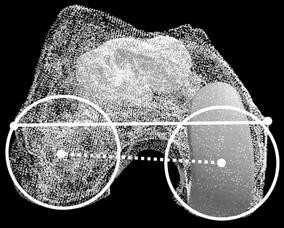

Seventeen osteoarthritic knees were tested before and after unicompartmental arthroplasty using a three-dimensional to two-dimensional registration technique tracking the transepicondylar axis to calculate translation and rotation of this axis. Results were compared for the seventeen knees before and after arthroplasty and were compared to the normal knee as measured in our previous study.

Fig. 1